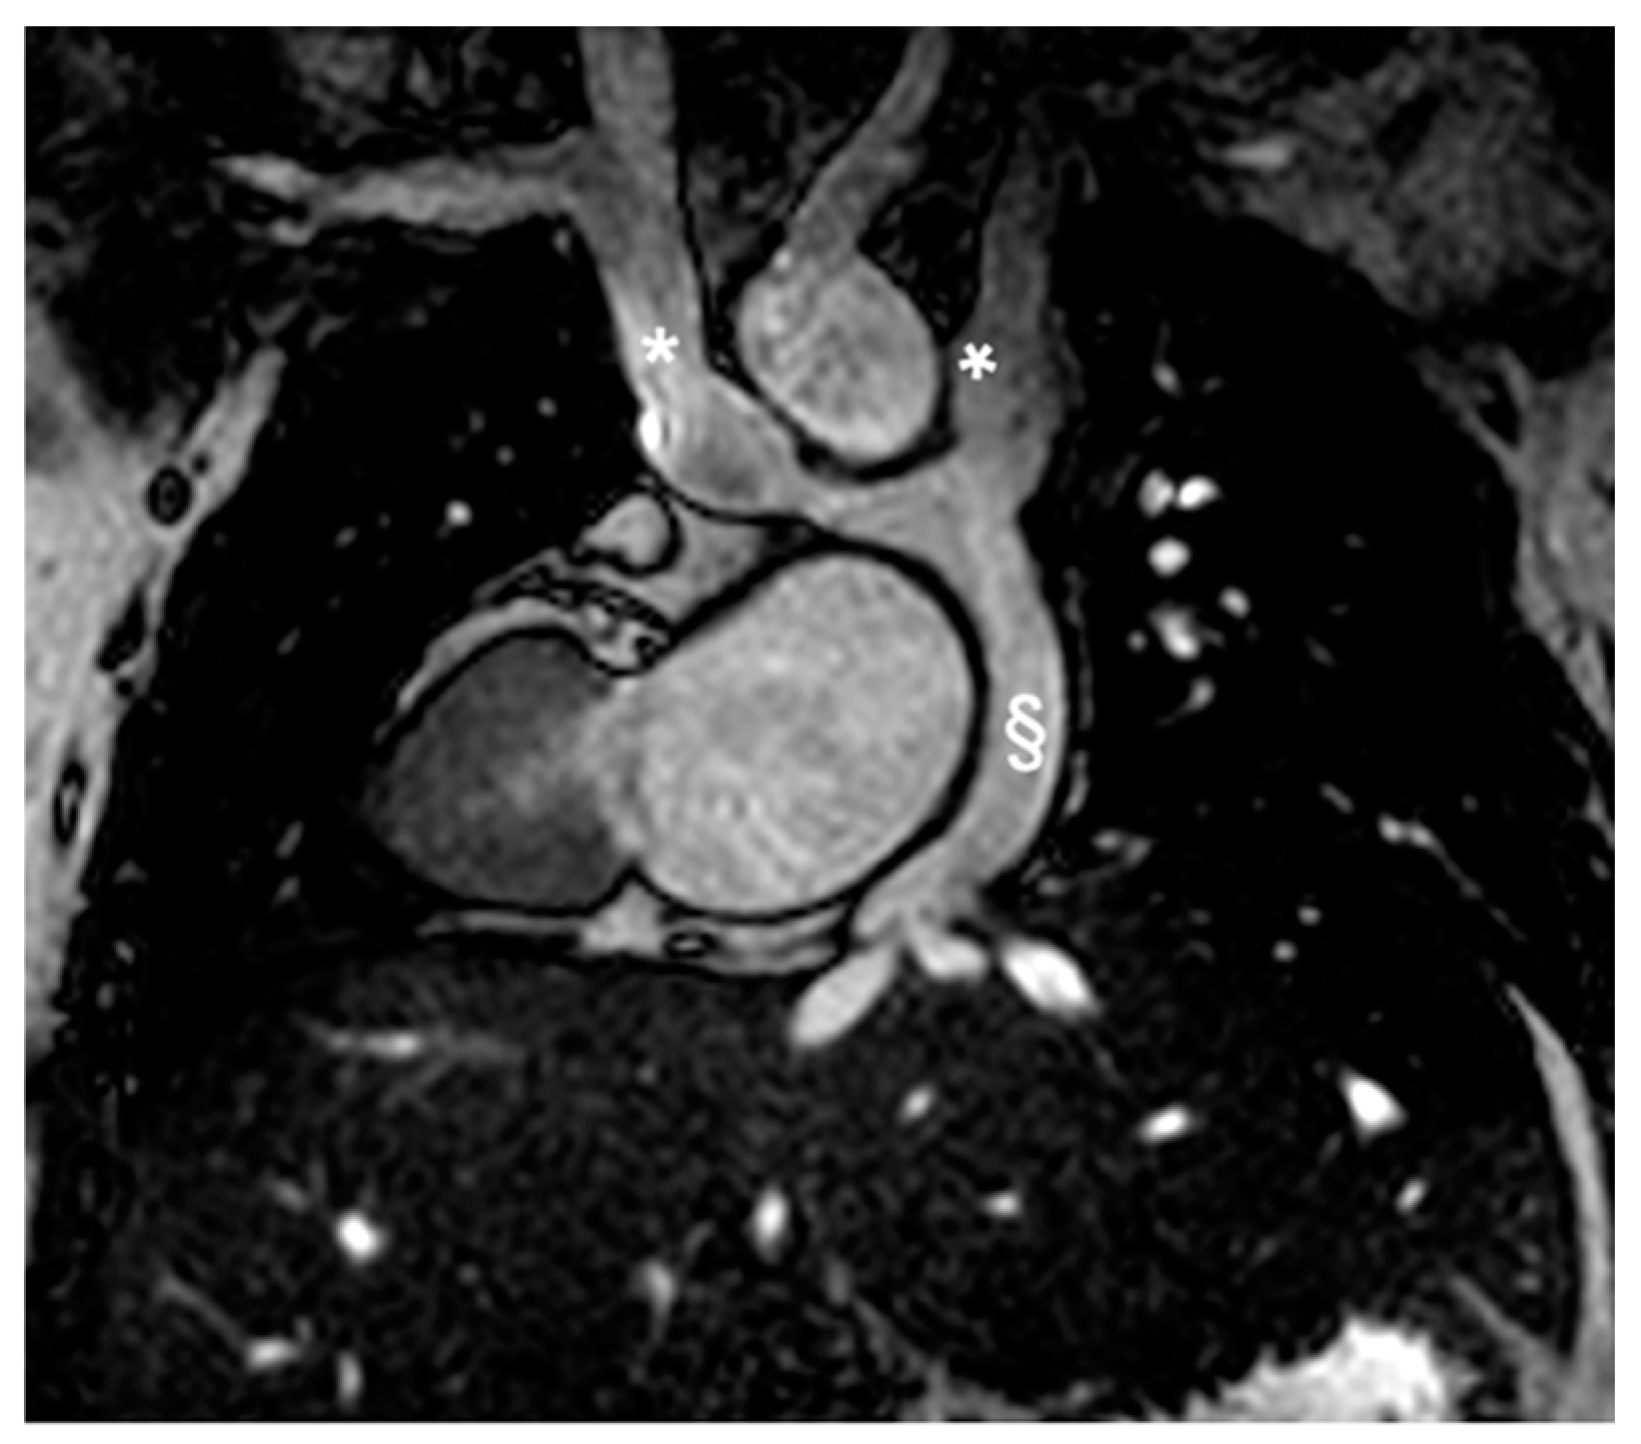

2.2.2. Congenitally Corrected Transposition of Great Arteries (cc-TGA)